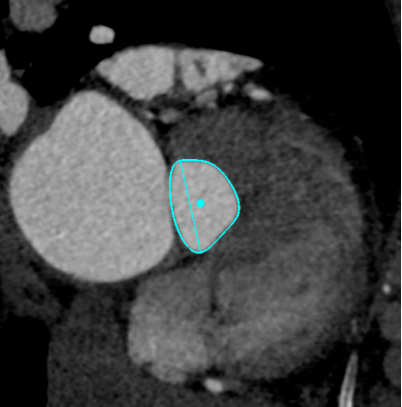

Annulus

长径: 24.8 mm

周长: 68.6 mm

面积: 352.3 mm²

LCA

下缘高度 7.1mm

上缘高度 11.9mm

瓣叶长度 11.8mm